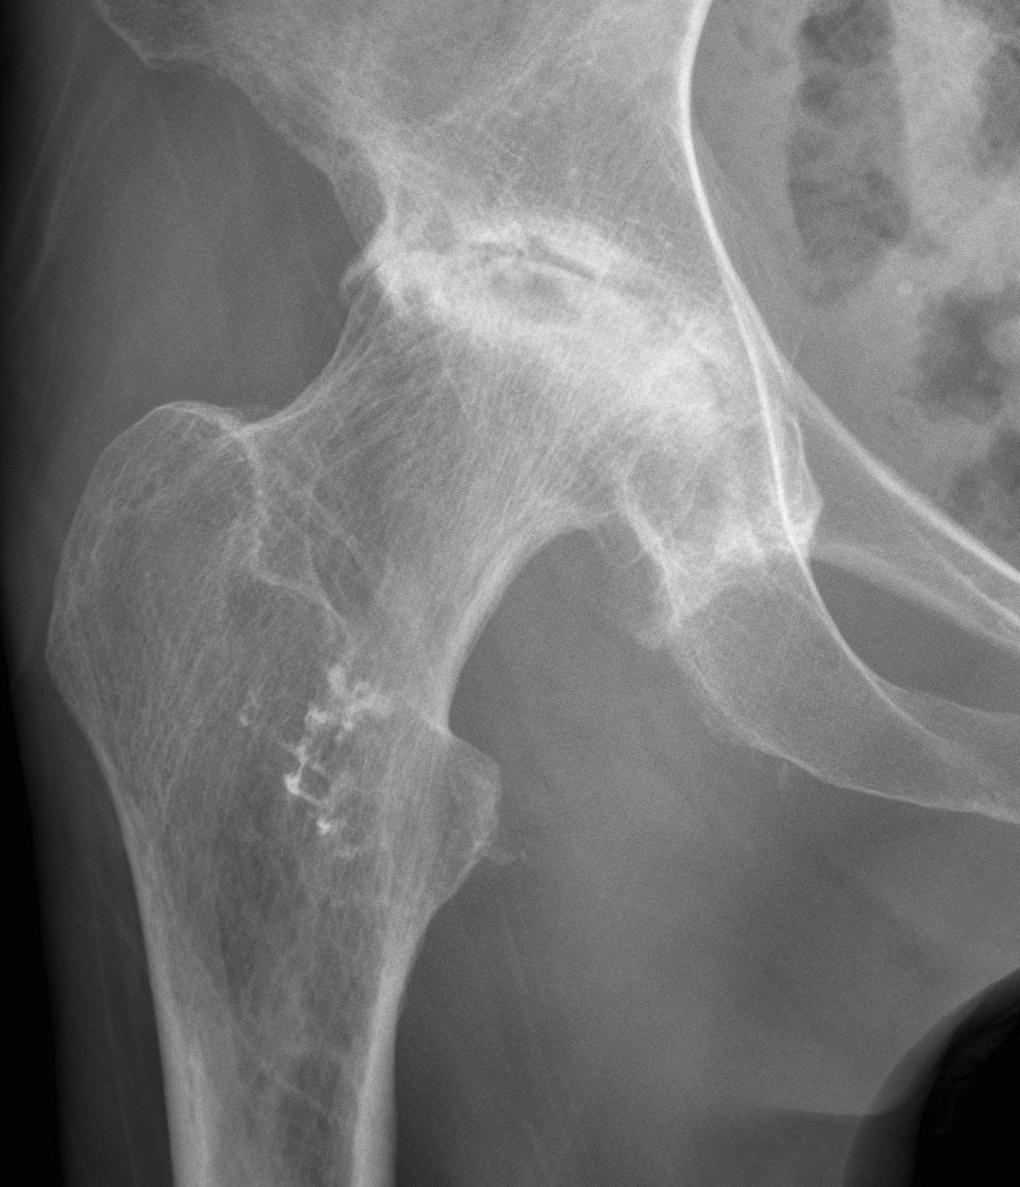

Xray

Stage IV: Collapse with osteoarthritis